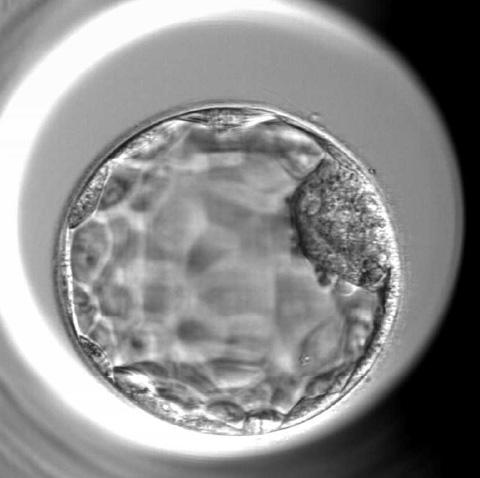

子宮内膜上皮あるいは卵管上皮より分泌されるEVsが胚発生、免疫(細菌叢)、着床などに果たす役割を研究しています。着床前期胚から分泌されるEVsについては、着床における役割、胚の質的(発生)マーカーとしての可能性なども検討しています。さらに、間葉系幹細胞から分泌されるEVsや多血小板血漿(Platelet-rich plasma: PRP) に含まれるEVsが子宮内膜や胚に与える影響を検討し、胚発生、卵管・子宮内細菌叢、着床不全などを改善するか、あるいは卵巣予備能の回復に寄与するかについて検討しています。いくつかの研究課題では、実中研や国立成育医療研究センターの先生方にお力添えいただき、共同研究を行っています。

胚盤胞移植の妊娠率は移植あたり30~60%であり、すべての移植胚が生児に至るわけではありません。私たちは、GM-CSFというサイトカインを用いて移植直前の胚盤胞を刺激することで、生産率が 約10%向上することを世界で初めて見出し、国際誌に報告しました。現在、この胚移植法の有効性を証明するため、多施設共同の前向き試験を開始しており、保険適用による社会実装と、日本の生殖補助医療の国際発信に取り組んでいます。